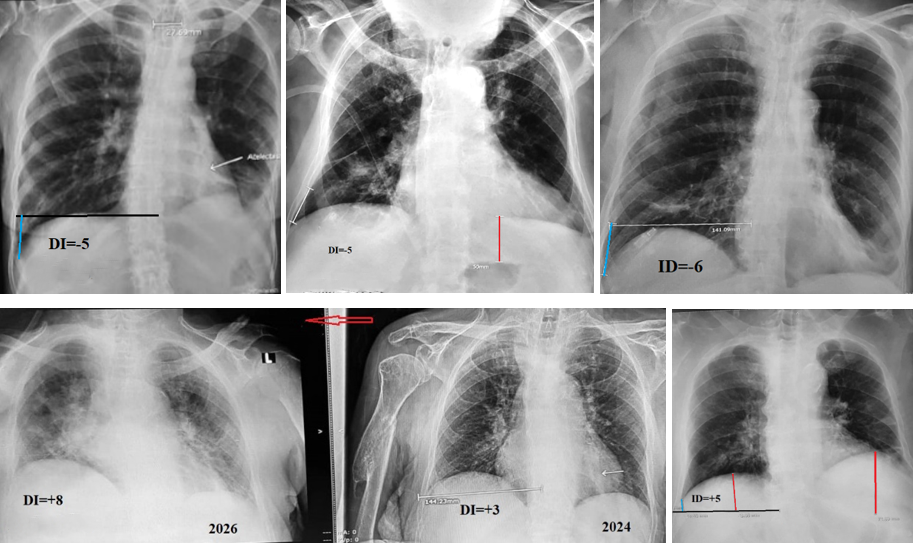

Atelectasis of the right lung was diagnosed on admission in 30 patients. Most of them were referred from other hospitals with a diagnosis of recurrent aspiration and had repeatedly received antibiotic therapy during febrile episodes. A representative example is shown in Figures 2a and 2b. In 21 of the 30 patients, right lung volume was markedly reduced compared with normal. This was manifested by elevation of the right diaphragmatic dome, rightward displacement of the cardiac silhouette, and a clear reduction in right lung volume relative to the left. In these patients, the diaphragmatic index ranged from 6 to 16 (mean, 12.4) (Figure 2b). Typical radiographic signs of atelectasis were present in 17 of these 21 patients, while in 4 cases the findings were equivocal. In these latter cases, an increased DI indicating significant reduction in right lung volume allowed confirmation of the diagnosis of atelectasis. In three patients with right-sided atelectasis, the DI values were within the normal range (2 to +5). In two of these cases, hyperinflation of the right upper lobe was present (Figure 2c), whereas in one case there was a marked rightward mediastinal shift (Figure 2d). Despite normal DI values, the conventional radiographic findings in these three patients were sufficiently convincing to establish the diagnosis of atelectasis. During follow-up, six patients developed atelectasis of the left lung. In four of these six patients, conventional radiographic signs of left-sided atelectasis were absent (Figure 2a). In these cases, the diagnosis of atelectasis was established solely based on a DI value greater than 5 (Figure 1a) (Table 1).

Figure 2. Chest radiographs showing atelectasis of the lower lobe of the right lung. (a). Right lower lobe atelectasis with gas-filled bronchiectasis (arrows). DI=+9 indicates right lung volume reduction despite the absence of radiographic evidence of atelectasis, which is due to the development of atelectasis on the other side. (b). The same patient showed signs of right-sided atelectasis on an X-ray 3.5 months ago. There was no pathology over the left dome of the diaphragm. He was treated as a patient with pneumonia using Intrapulmonary Percussive Ventilation (IPV) for sputum removal, which resulted in the spread of infection to the left lung [7]. (c). The right dome of the diaphragm is higher than the left. It has risen to the level of the hilum of the right lung, but the cardiac shadow is shifted to the left. DI=+ 2 is within the normal range because of hyperinflation of the right upper lobe, as evidenced by increased lucency and rare pulmonary pattern. (d). A triangular shadow of atelectasis of the lower lobe of the right lung is visible. DI= 0 is within normal limits because the cardiac shadow and mediastinum are shifted to the right, and the upper lobe of the right lung is stretched in the craniocaudal direction.

The statistical summary of different variants of right lung atelectasis is presented in Table 1. The use of the diaphragmatic index increased the diagnostic accuracy of right-sided atelectasis in 4 of 21 patients and enabled detection of left-sided atelectasis resulting from disease progression in 4 of 6 patients. Overall, incorporation of the DI provided additional diagnostic information in 8 of the 30 patients (27%). Notably, none of the 30 cases demonstrated convincing radiographic evidence of hyperinflation of the left lung.

The most common radiographic findings on admission were those typically described in the literature: leftward displacement of the cardiac silhouette, elevation of the left hemidiaphragm, disappearance or marked reduction of the left pulmonary hilum due to cardiac rotation, decreased volume of the left lung, and hyperinflation of the right lung (Figure 3a). Hyperinflation, defined as an increase in right lung volume quantified by a decrease in the diaphragmatic index (DI) below the lower limit of normal (i.e., < 0), was detected in 18 of 22 cases, with a mean DI of −4.5. The use of a mathematical parameter increased the reliability of this sign and allowed assessment of its dynamics. In many cases, the atelectatic shadow was visible against the background of the cardiac silhouette (Figure 3a, c, d). In 4 of the 22 patients with a negative DI, several radiographic features did not correspond to the typical pattern. In one case, both diaphragmatic domes were at the same level despite atelectasis of the left lower lobe (Figure 3b). In three cases, the right hemidiaphragm was higher than the left (Figure 3c). In four patients with a positive DI, the right hemidiaphragm was also higher than the left (Figure 3d, e). In two of these patients, serial radiographs documented progression of the process, with an increase in DI indicating the development of atelectasis in the right lung (Figure 3d–e). In six patients with left lung atelectasis, the gastric air bubble was not located directly beneath the diaphragmatic dome but was separated from it by 3–7 cm. In four of these cases, the gas bubble was deformed, as if compressed from above (Figure 3b).

Figure 3. Radiographs of patients admitted to atelectasis at the base of the left lung. (a). Typical picture of atelectasis in the left lung (arrow) with hyperventilation of the right lung (DI=-5). (b). Patient with increased volume of both lungs (DI=-5). Both diaphragms are at the same level. Atelectasis of the lower lobe on the left displaces the gas bubble of the stomach downwards. Inflammatory changes on the right, together with other signs, indicate atelectasis also at the base of the right lung. (c). In a patient with atelectasis on the left, the right dome of the diaphragm is higher than the left one. Above it, there are inflammatory changes confirming atelectasis also at the base of the right lung. (d-e). In 2024, atelectasis was visible on the left and atelectasis was suspected on the right. In 2026, atelectasis was evident on both sides. (f). Leftward displacement of the heart, elevation of the left dome of the diaphragm, and a decrease in the volume of the left lung are accompanied by an inflammatory reaction in the root of the right lung and the absence of hyperinflation. This confirms atelectasis on the right (Table 2).